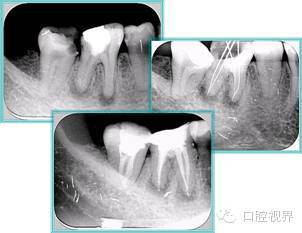

5. 不良根管充填物

常见不良根管充填物有干髓、塑化、塑化 + 根充和不良根充。

口腔H锉怎么消毒根管治疗的细节把握(细节决定成败)_https://www.jmylbn.com_新闻资讯_第21张

( 1 )干髓。

干髓治疗时,开髓后髓腔里注入甲醛甲酚 FC 灌髓,三聚甲醛固定,髓室底放置三聚甲醛缓慢释放,进行根管无害化处理。髓腔缓慢坏死,机体代偿出现根管钙化。如果患者在封闭腔出现出现病变,由于髓腔钙化,根管堵塞严重,检查治疗比较困难。

解决方法:1 )彻底去除坏死的牙髓组织。2 )借助化学性药剂,如 EDTA 等。3 )初锉选用8#或10#K 锉,平衡力法探察到工作长度 , H锉上下提拉法使根管扩大,提高工作效率。

口腔H锉怎么消毒根管治疗的细节把握(细节决定成败)_https://www.jmylbn.com_新闻资讯_第22张

左图和上图为干髓治疗后牙齿,龋齿疏通后进行根管充填。

( 2 )塑化。

传统的治疗思维:塑化治疗后患者需将塑化液清理干净,达到彻底根管治疗目的。 口腔H锉怎么消毒根管治疗的细节把握(细节决定成败)_https://www.jmylbn.com_新闻资讯_第23张

目前的治疗思维:以前塑化治疗效果好时不必清理干净塑化液。对于根尖没有病变的患者,可借助溶解剂建立通路;根尖存在病变的患者往往是塑化治疗不理想患者,需要彻底打通通路。